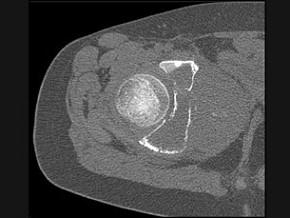

问题 男,15岁,右髋部疼痛、红肿,有压痛,皮温增高,结合图像,最可能的诊断是 ( )

选项 A、转移性神经母细胞瘤 B、骨结核 C、急性骨髓炎 D、Ewing肉瘤 E、骨肉瘤

答案 D